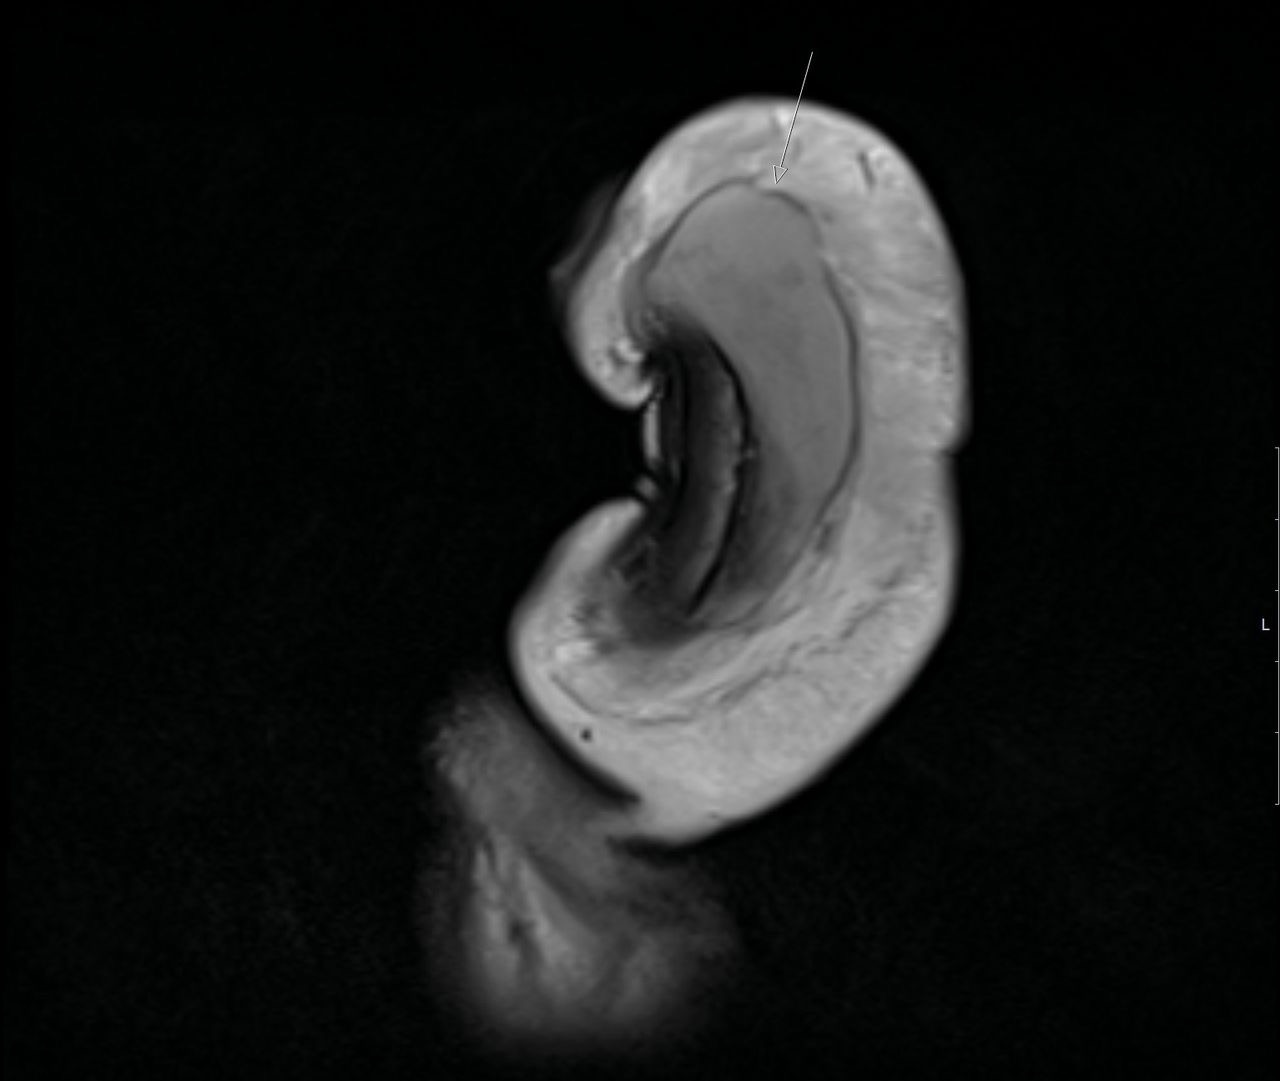

МРТ полового члена

Демонстрация гематомы, которая примыкает к дистальному концу правому кавернозному корпусу.